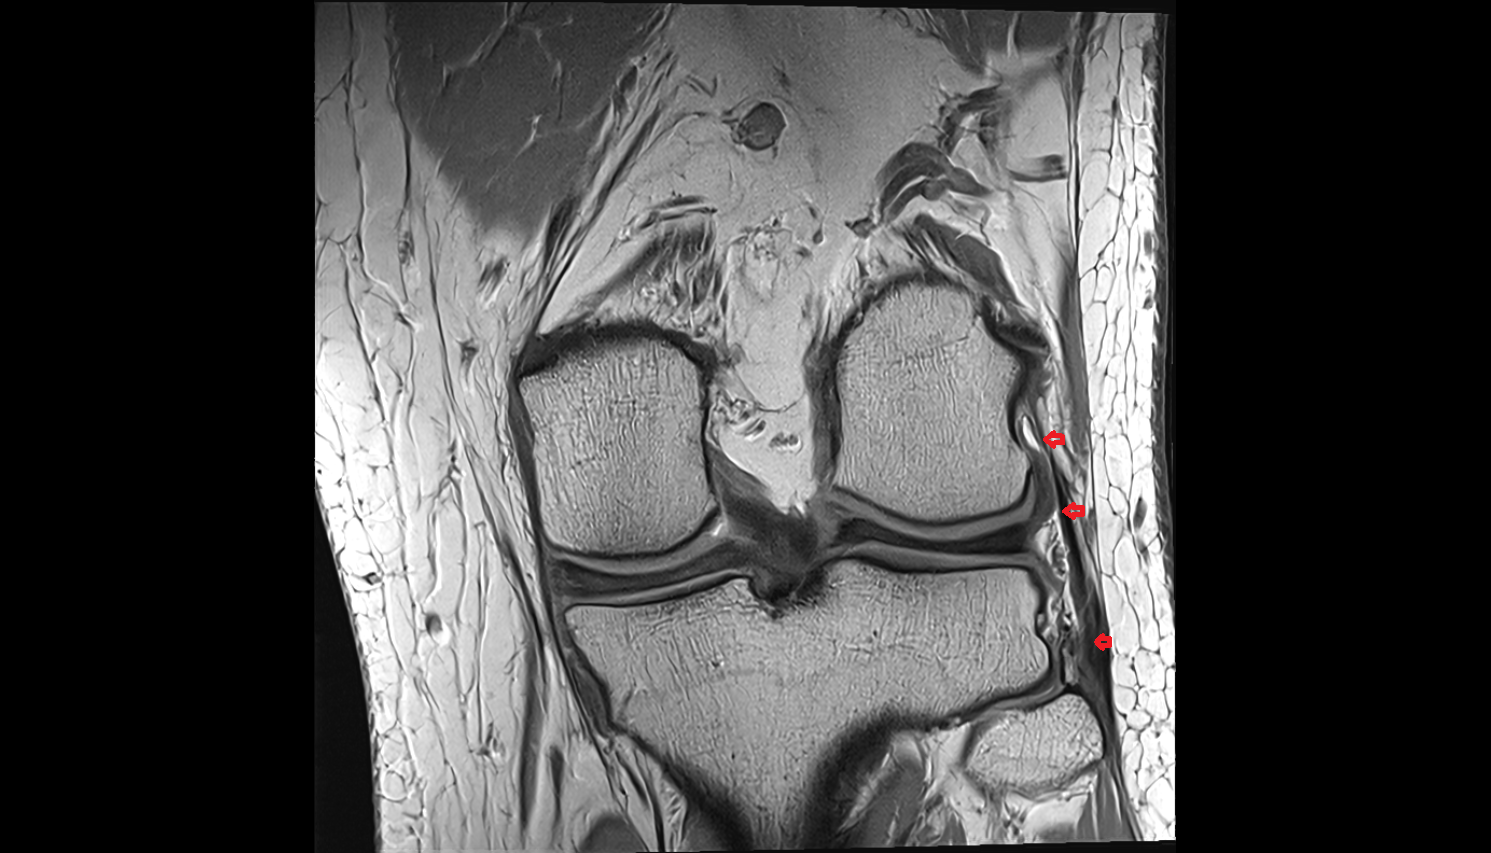

- Medial meniscus

- Lateral meniscus

- Medial collateral ligament

- Lateral collateral ligament

- Anterior cruciate ligament

- Posterior cruciate ligament

- Knee Joint